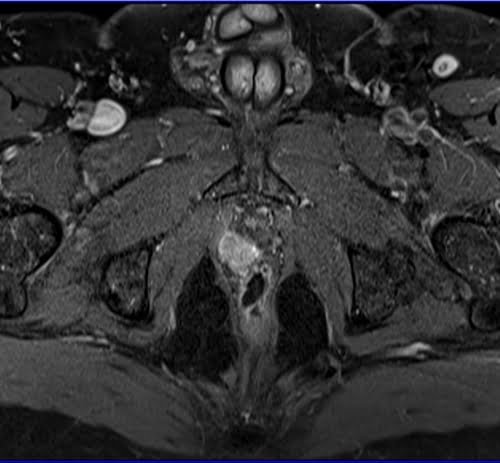

Prostatectomy patients prostate MRI T1 fat sat post contrast axial high resolution images